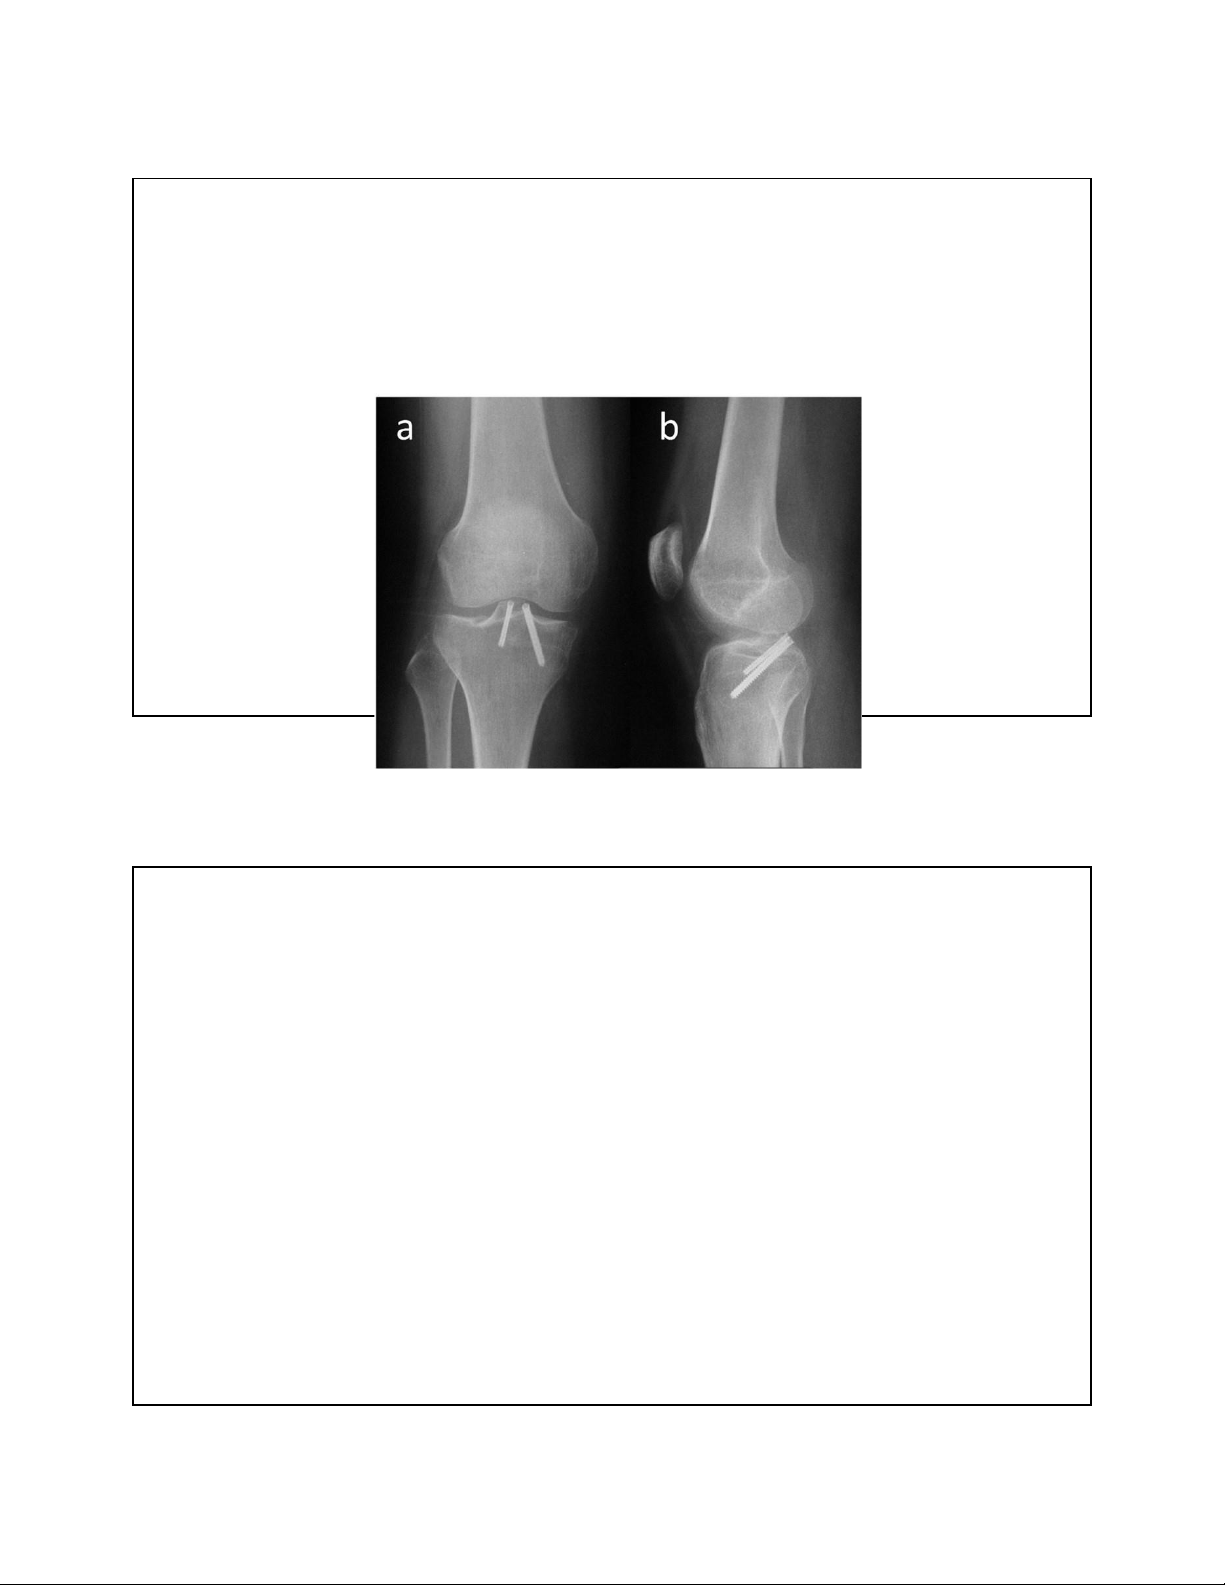

3. TỔN THƯƠNG DÂY CHẰNG – BONG CHỖ BÁM lOMoAR cPSD| 22014077 7/15/2023 12

3. TỔN THƯƠNG DÂY CHẰNG - ĐÍNH LẠI BONG CHỖ BÁM 13 ĐAU KHỚP GỐI

• Có tác dụng kéo dài ặc biệt là BN còn trẻ 27 CẮT XƯƠNG SỬA TRỤC

• Mục ích: chuyển lực từ khoang bị thoái hoá sang khoang lành

• Chậm tiến trình thoái hoá, giảm au

• Làm chậm quá trình thay khớp Chọn bệnh • <60t

• Khớp chè ùi còn tốt??? • Thoái hoá 1 khoang???

• Gối vững ( dây chằng còn nguyên vẹn) 28 lOMoAR cPSD| 22014077 7/15/2023 Cắt xương sửa trục Chống chỉ ịnh: >60 tuổi Béo phì Hư 2-3 khoang